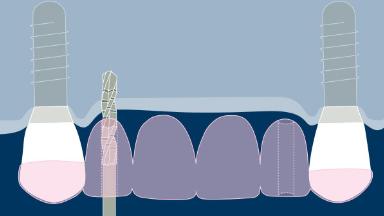

A implantodontia evoluiu consideravelmente desde os protocolos de tratamento precoce, nos quais o posicionamento dos implantes não era considerado crítico para um resultado bem-sucedido. Nesta abordagem orientada cirurgicamente, os implantes foram instalados onde havia osso suficiente para apoiá-los, e a ênfase estava no resultado funcional. Esta imagem clínica mostra três implantes adjacentes suportados por coroas unitárias. Isso proporcionou ao paciente um bom resultado funcional, mas a estética ao nível da emergência do implante foi apenas uma consideração secundária. Na implantodontia moderna, o resultado estético geral é de igual ou maior importância para o paciente. Os resultados estéticos estão intimamente relacionados a um alto nível de precisão no posicionamento dos implantes dentários de suporte. Uma segunda imagem clínica mostra um exemplo de uma coroa unitária implantossuportada no incisivo central superior esquerdo, onde o posicionamento cuidadoso do implante permitiu que o perfil de emergência imitasse o do incisivo central natural. Guias de transferência para orientar a instalação precisa tridimensional do implante são críticos para alcançar esse resultado. Este Módulo de Aprendizado ITI discutirá o uso rotineiro de guias de transferência na implantodontia.